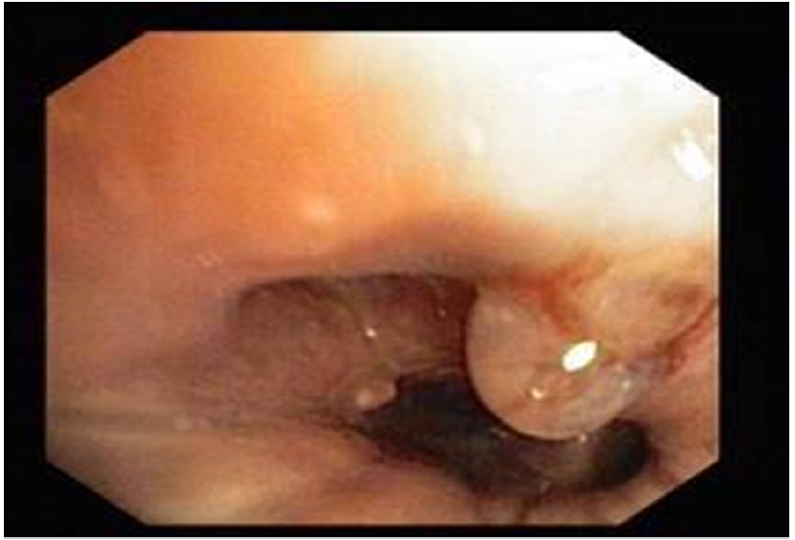

・耳鼻科へ緊急コンサルトされ、喉頭ファイバー検査を実施

◦声門下領域に管腔外病変が疑われた